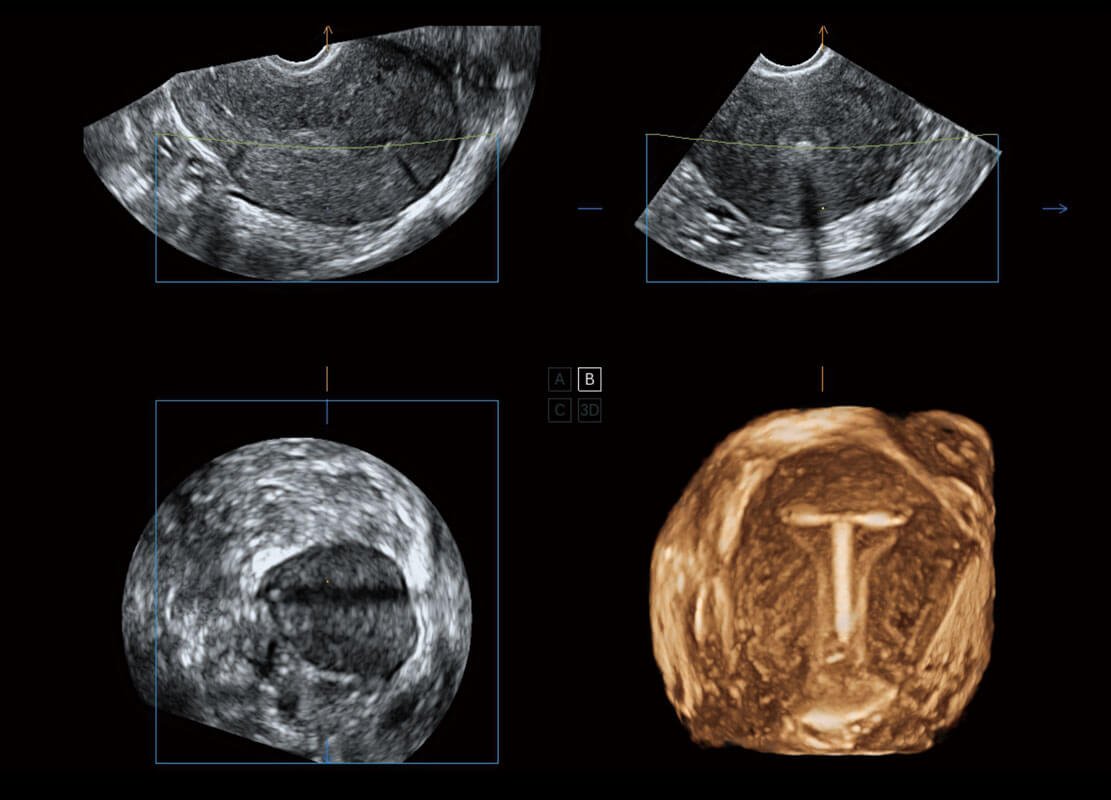

• 腔内三维-宫内节育器

• 腔内三维-光影成像